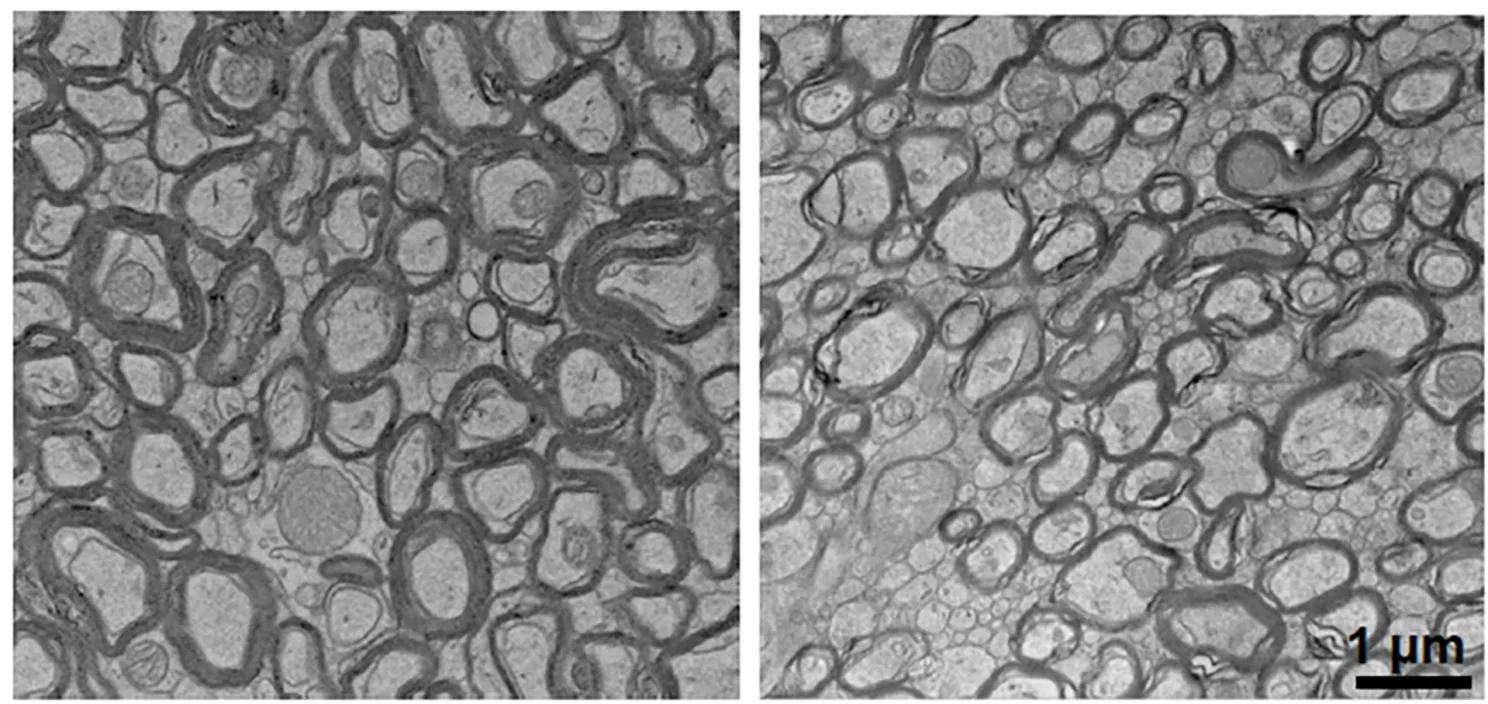

与正常小鼠(左)相比,锂水平的下降会导致神经元外包裹的髓鞘变薄(右)。(图/Yankner Lab)